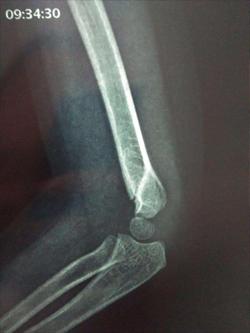

经X光片正位片侧位片检查结果,显示肱骨远端移位,确定为肱骨髁上骨折。其实肱骨髁上骨折是比较常见的儿童骨折,像小宝的情况就是由于直接的*力暴**撞击导致。另外,如手掌受到冲击,比如摔倒的时候用手去撑地面,力量自下而上传递,也有可能导致肱骨髁上骨折。

通常刚发生肱骨髁上骨折时,骨折移位程度较轻微,受伤部位肿胀不明显;如果再受到别的力量震动,会加重移位程度,引起肿胀、畸形、瘀斑、水疱等,疼痛感强烈,手肘无法活动。

针对小宝的情况,由于撞击不是很重,加上妈妈处理得当,移位不是很严重,复位后用石膏托固定一个月,每两周复查,基本上可以痊愈。

而如果是严重的肱骨髁上骨折,如中尺侧有压缩的要手术治疗,因为复位不好容易导致畸形愈合,形成肘内翻。对于完全移位骨折,就要手术治疗,闭合复位,行经皮克氏针固定才行。